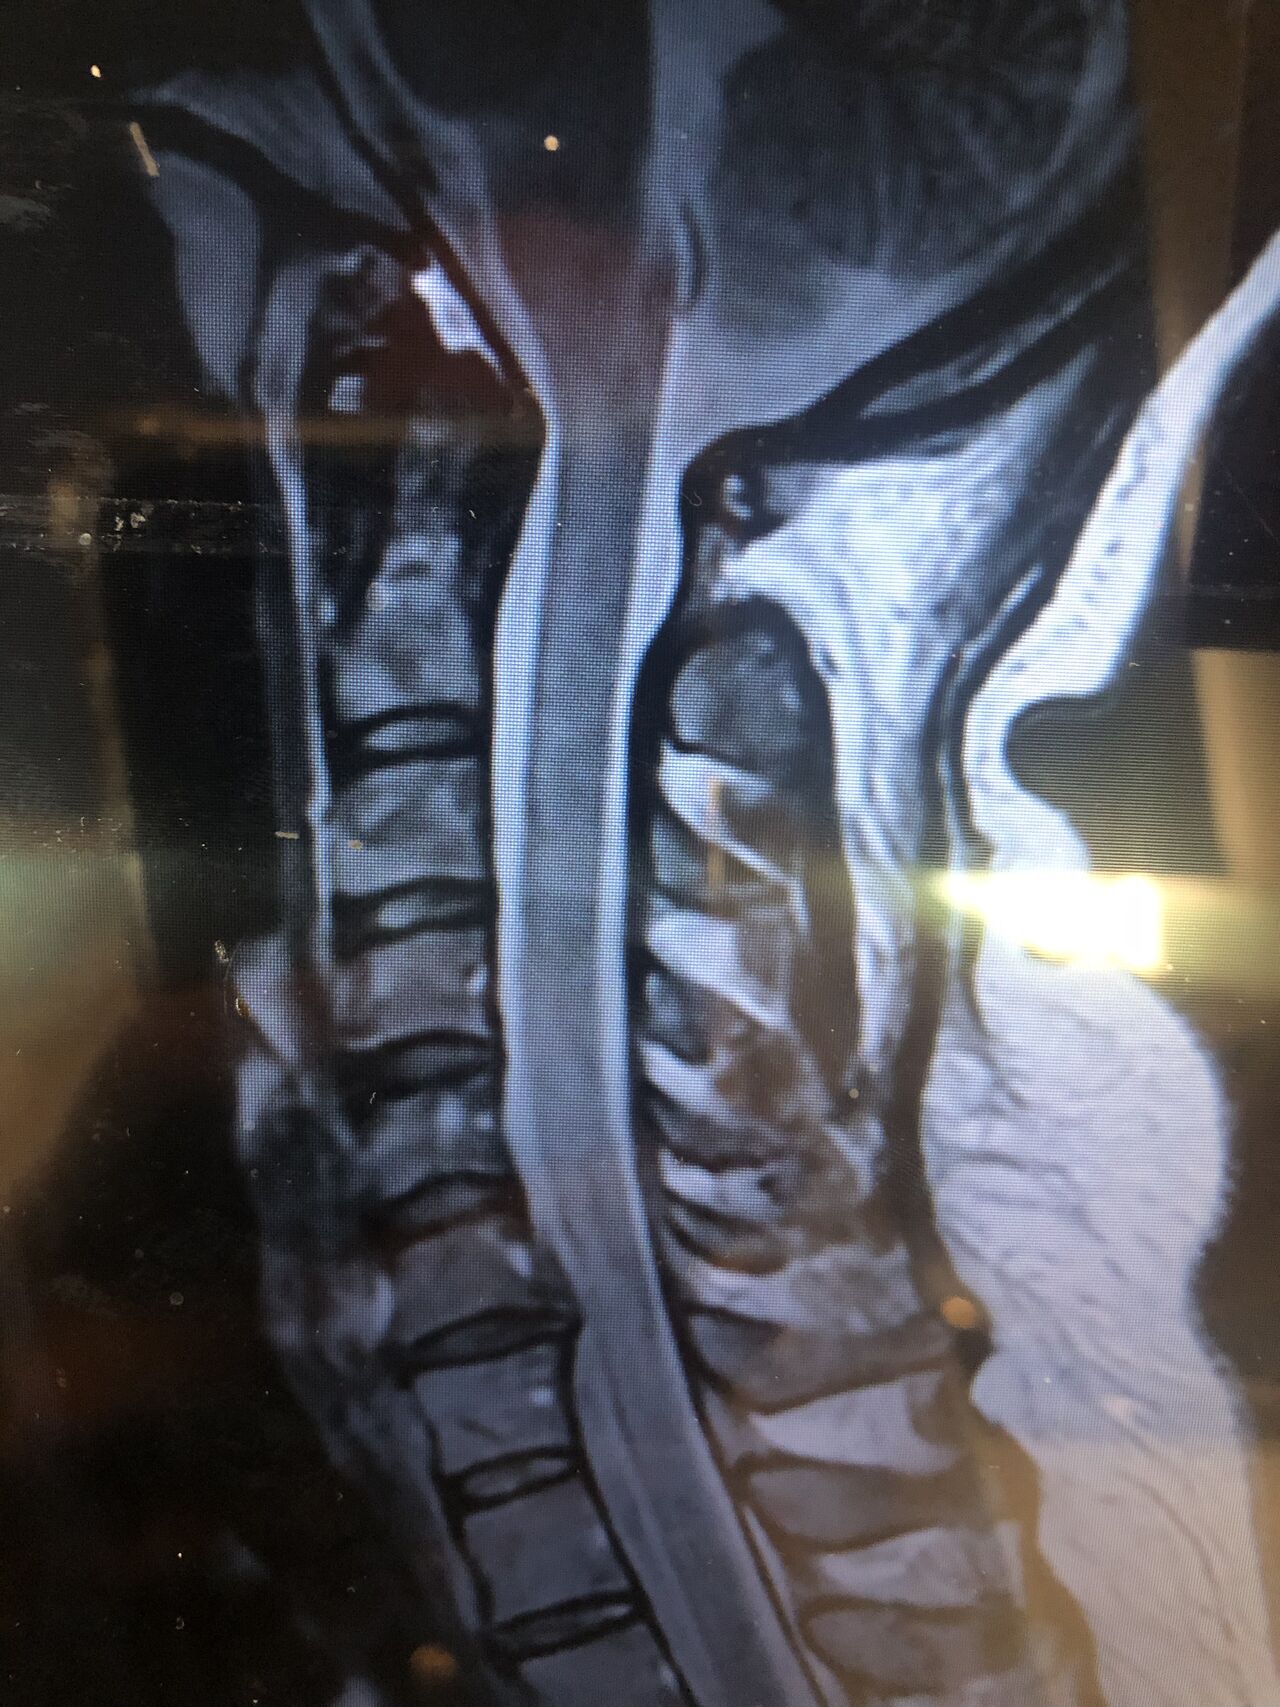

41 years old man presented to my clinic in October 2023 with acute and sever R neck pain with radicular pain to his R upper extremity along C6 dematom since 2 weeks ago. Examination didn’t show any upper motor signs. Was suggested urgent surgery

I ordered EMG/ NCV : showed mild R C6, C7 irritation without any active axonal loss

In his MRI was reported R. para R. IVF Massive extrusion. I decided to control his pain and manage this patient with reevaluation of patient every other session. For 5 sessions i just used acupuncture and laser and IFC and mild adjustments to his R. T3-T7 and mild arthosteem to above and below involved segment. Cervical adjustment considered contraindicated for this patient. From session 6th- 8th i started to use mild/gentle cervical decompression. He used soft cervical collar all the time. His pain decreased by 80 percent

I gave him cervical traction pump to be used 3-5 times per day at home for the next 3 months and i released the patient. He was evaluated every week once for one month and after that every 2 weeks. After 3 month I repeated MRI. Size of the herniated disc was reduced greater than 50 percent. Asked him to do another mri in 6 months

In general: Precise selection of the patients, examination,diagnosis, plan of management, reevaluation and treatment can be done by doctors of chiropractic for the patients with spinal disc herniation and stenosis Moreover giving reasonable time to these kind of patients under direct supervision by their chiropractic doctors can prevent unnecessary surgery. Proper selection of these kind of patients is another important fact that can be done precisely by chiropractors.

MRIs before and after proper management of this patient: